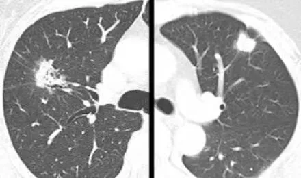

SPN评估关键,薄层CT可清晰展现结节细节,如密度(实性、磨玻璃、混合性)、边缘(光滑、分叶、毛刺)、内部结构(有无空洞、钙化)等特征。如磨玻璃结节伴实性成分、边缘毛刺征、胸膜牵拉等常提示恶性可能;良性结节钙化多呈中心性、层状或爆米花状。增强CT依据结节强化程度辅助判断血供,恶性结节多呈中度至高度强化。

影像学特征分析及随访:如纯磨玻璃结节早期肺癌概率相对低,但随访中若出现密度增加、实性成分增多常提示恶变;分叶征、毛刺征、胸膜凹陷征等在肺癌中多见,而爆米花样钙化多见于错构瘤等良性病变。对于不确定结节,规律的CT复查观察结节大小、形态变化。实性结节增长缓慢,倍增时间常>400天;恶性磨玻璃结节倍增时间约200 - 400天,若短期内迅速增大多为炎性。